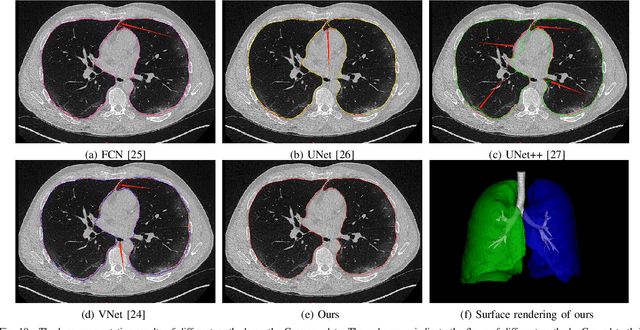

Abstract:A novel coronavirus disease 2019 (COVID-19) was detected and has spread rapidly across various countries around the world since the end of the year 2019, Computed Tomography (CT) images have been used as a crucial alternative to the time-consuming RT-PCR test. However, pure manual segmentation of CT images faces a serious challenge with the increase of suspected cases, resulting in urgent requirements for accurate and automatic segmentation of COVID-19 infections. Unfortunately, since the imaging characteristics of the COVID-19 infection are diverse and similar to the backgrounds, existing medical image segmentation methods cannot achieve satisfactory performance. In this work, we try to establish a new deep convolutional neural network tailored for segmenting the chest CT images with COVID-19 infections. We firstly maintain a large and new chest CT image dataset consisting of 165,667 annotated chest CT images from 861 patients with confirmed COVID-19. Inspired by the observation that the boundary of the infected lung can be enhanced by adjusting the global intensity, in the proposed deep CNN, we introduce a feature variation block which adaptively adjusts the global properties of the features for segmenting COVID-19 infection. The proposed FV block can enhance the capability of feature representation effectively and adaptively for diverse cases. We fuse features at different scales by proposing Progressive Atrous Spatial Pyramid Pooling to handle the sophisticated infection areas with diverse appearance and shapes. We conducted experiments on the data collected in China and Germany and show that the proposed deep CNN can produce impressive performance effectively.